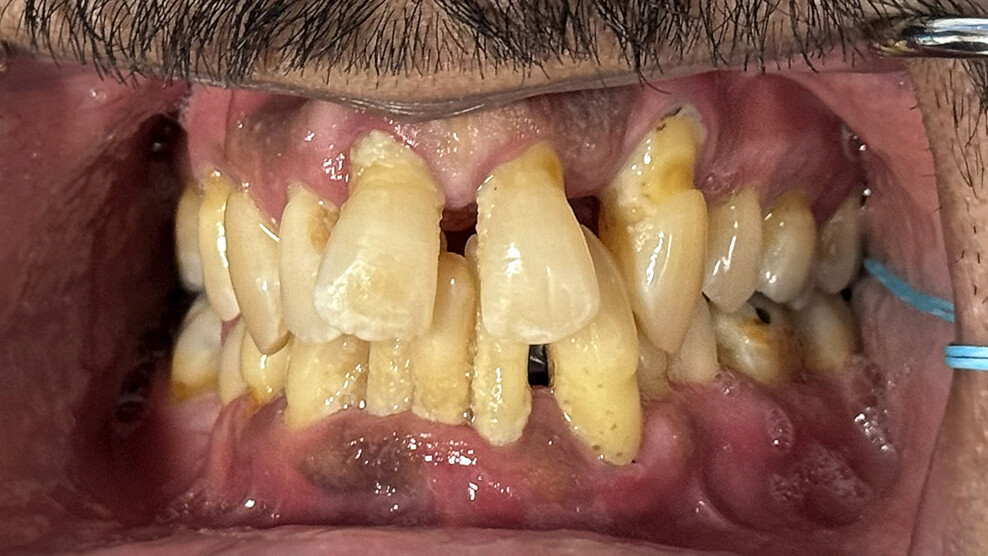

Fig. 1a: Pre-op situation. Intra-oral retracted view of the maxillary teeth, showing advanced periodontal disease and anterior spacing. (All images: Dr Scott D. Ganz)

A 49-year-old male patient presented with failing maxillary and mandibular teeth. The findings of the clinical and radiographic examinations were severe periodontal disease, generalised bone loss, anterior spacing and tooth mobility, in addition to overall poor hygiene maintenance (Figs. 1a & b & 2a). The patient was informed of the findings, and several treatment options were discussed, including complete and/or partial dentures, implant-supported overdentures and implant-supported fixed restorations. After discussion regarding the options, the patient decided on full-arch implant-supported fixed restorations.